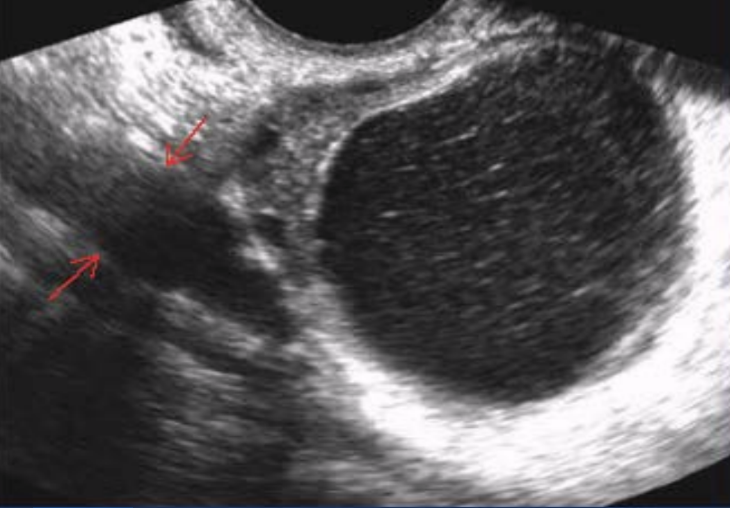

What is the structure the arrows are pointing to?

a. Ovary

b. Iliac artery

c. Psoas muscle

d. Fallopian tube

Psoas muscle